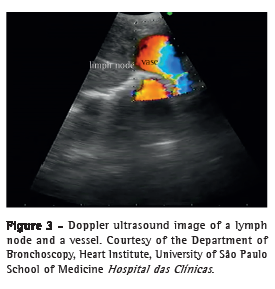

Wang needle (21G) transtracheal/transbronchial aspiration is still often used in conventional bronchoscopy because of its ease of use, safety, and low cost; however, up to 43% of the collected samples are unsatisfactory for diagnosis.(18) Available in Brazil, EBUS needles measure 22G in diameter, are provided with a protective sheath, have an exposure of approximately 4 cm, and have two to three safety locks to reduce the risk of accidents related to aspiration (vessels and other mediastinal structures) and the risk of perforation of the working channel of the device. The needle set includes a dedicated valve that fits into the working channel port of the device, thereby making it possible to connect the needle to the EBUS equipment. Once the needle is introduced into the working channel, it should be pushed until it fully fits into the valve connected to the device and is locked. The sheath should remain exposed until it is seen bronchoscopically, and only then can the safety lock of the needle be released. The needle should be advanced through the tracheobronchial wall in order to aspirate paratracheal or peribronchial lymph nodes or lesions (Figure 4).